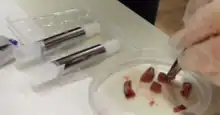

Creating PCLS is a meticulous process that involves several essential steps. The use of Compresstome vibratomes is crucial in ensuring the production of precise and high-quality slices for research purposes.

The basic steps involved in preparing PCLS using Compresstome vibratomes include:[8]

- Tissue selection

- Start by carefully selecting liver tissue from the desired species, such as rodents or humans, ensuring the tissue is of high quality and health.

- Tissue embedding

- To facilitate slicing and maintain tissue structure, the liver tissue is typically embedded in a suitable medium, such as agarose or gelatin, into the specimen holder of the Compresstome vibratome.

- Slicing process

- The vibratome operates by oscillating a blade vertically at high frequencies while the tissue is submerged in a cutting solution. This mechanical oscillation creates thin and precise slices of tissue. Researchers can adjust cutting parameters, such as slice thickness, to meet specific experimental requirements. Typically, PCLS have thicknesses ranging from 200–500µm.

- Post-processing

- Depending on the research objectives, PCLS may undergo additional steps such as washing, culturing, or treatment with substances of interest, such as drugs or stimuli.